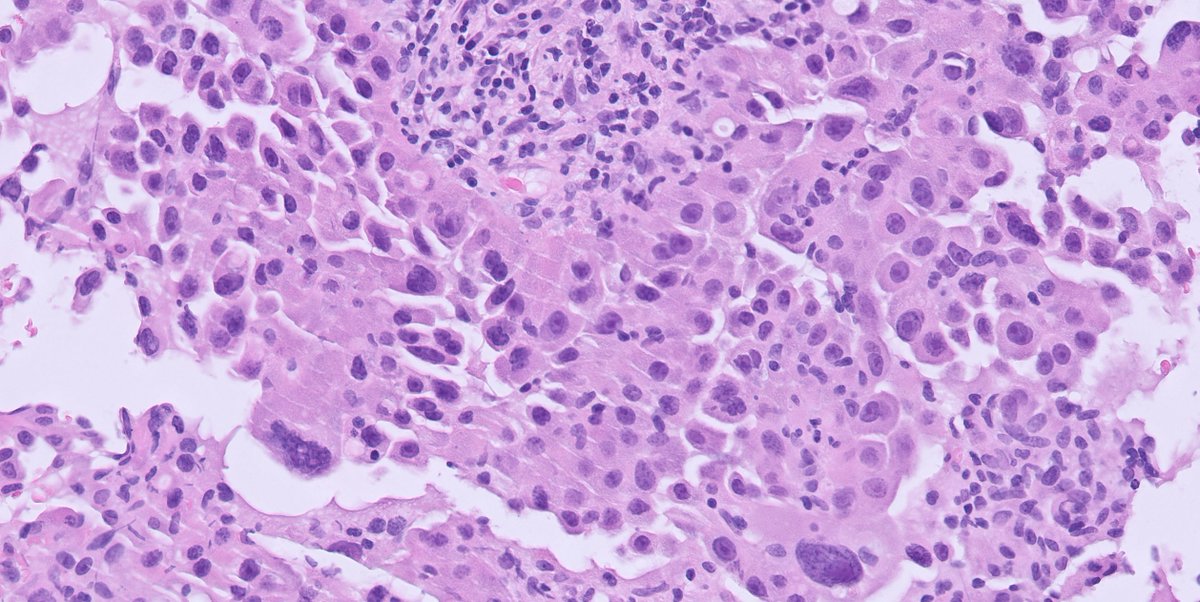

1/ Your favorite #breastpath topic....papillary lesions...core needle biopsy from a BI-RADS 5 lesion... What is your diagnosis #pathtwitter?

1/ Your favorite #breastpath topic....papillary lesions...core needle biopsy from a BI-RADS 5 lesion...

What is your diagnosis #pathtwitter?